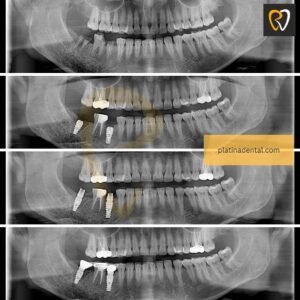

1️⃣ Single Tooth Implant in Hyderabad

Ideal when only one tooth is missing. The implant replaces the root, and a crown is placed over it for a natural appearance. A single tooth implant replaces a missing tooth without affecting adjacent teeth. If you need a single tooth implant in KPHB or Kondapur, early placement prevents bone loss and shifting.